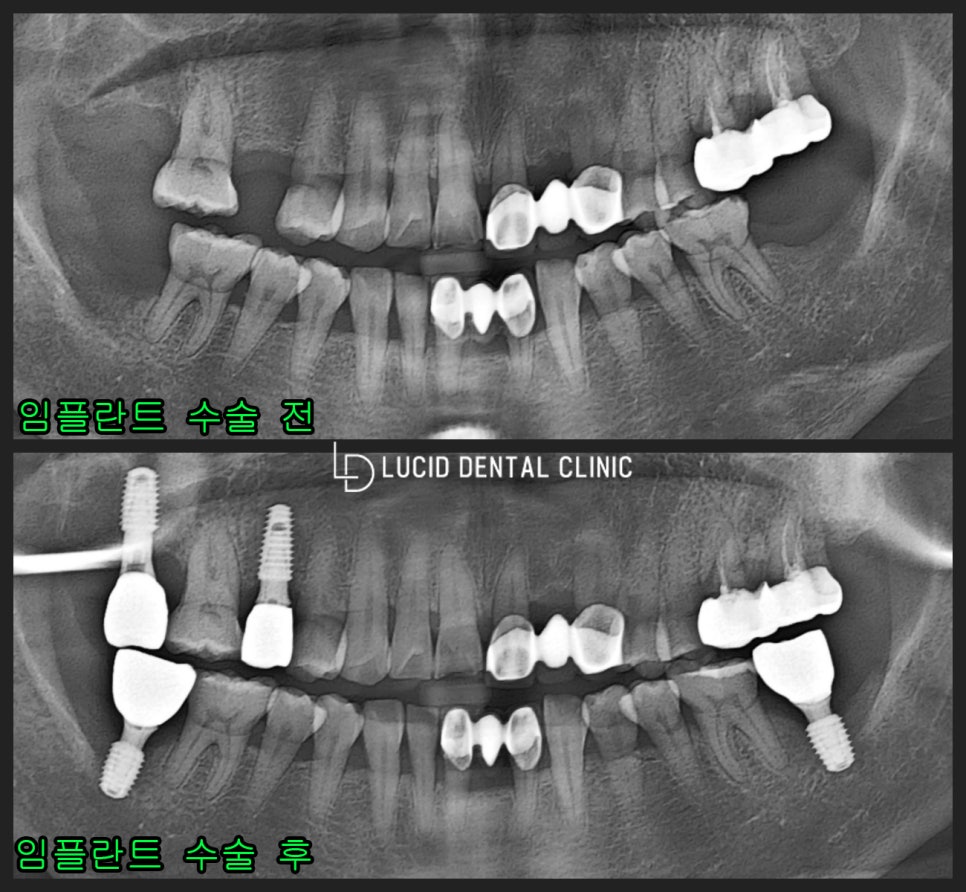

- 결과

사진과 같이 빈 어금니 부분을

픽스처를 통해 공간을 폐쇄하고

정출된 어금니 교합면을 정돈하여

올바른 교합으로 바꿔 두었습니다.

환자께서 저와 약속한 대로

구강 관리도 꼼꼼히 시행하고

정기 검진을 꾸준히 받으셨는데요

이전과 달리 밥 먹을 때마다

문제 없이 저작이 가능하다며

감사 인사를 전하셨습니다.